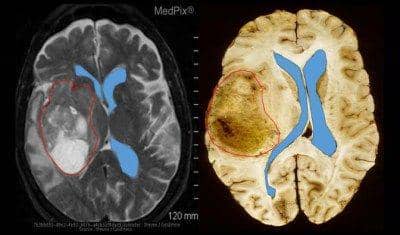

Glioblastoma merupakan jenis tumor yang menyerang sel otak dan tumbuh pada salah satu sisi otak. Tumor ini terbentuk dari sel berbentuk bintang di otak yang disebut, astrosit. Sekitar satu dari lima tumor yang dimulai di otak adalah glioblastoma ini. Menurut National Brain Tumor Society Amerika, angka harapan hidup rata-rata dari penyakit ini adalah 15 bulan hingga 3 tahun setelah didiagnosa.

Glioblastoma dikategorikan sebagai tumor ganas dan agresif karena perkembangan sel-sel tumor ini sangat cepat. Oleh karena itu tumor ini bisa sulit untuk diobati karena dalam tumor terdapat banyak jenis sel-sel abnormal yang berbeda-beda, yang mana sebagian dapat merespon dengan baik pada terapi tertentu dan sebagian sel lainnya tidak.

Apabila Glioblastoma tidak didiagnosis dengan segera dan cepat makan kekambuhan penyakit ini akan sering terjadi. Hal ini karena sel-sel tumor ini berkembang dengan cepat seiring bertambahnya usia. Apabila tidak ditangani sejak awal, sel-sel tumor dapat menyebar ke bagian otak lainnya.